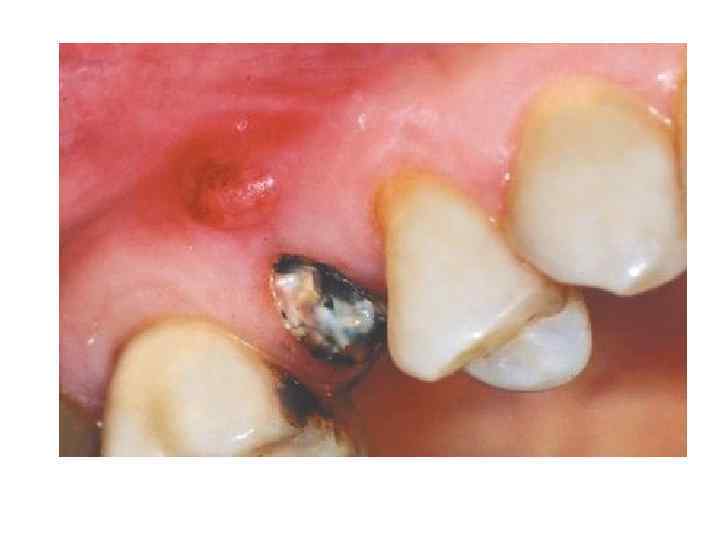

Клиническая картина. • Гранулирующий периодонтит является наиболее активной формой хронического периодонтита и дает весьма многообразную клиническую картину. Жалобы при гранулирующем периодонтите различны. Чаще больные жалуются на болезненность приеме твердой и горячей пищи, иногда боль усиливается при давлении. При гранулирующем периодонтите часто бывают обострения различной интенсивности. Активность воспалительного процесса проявляется периодическими болями в зубе при надавливании на него или накусывании

• Слизистая оболочка, покрывающая альвеолярный отросток в области верхушки корня зуба с гранулирующим очагом в периодонте, обычно слегка отечна и гиперемирована, при надавливании пинцетом или зондом на десну остается отпечаток инструмента. При вовлечении в патологический процесс прилежащих мягких тканей на слизистой оболочке возникает свищевой ход, который располагается чаще на уровне верхушки пораженного зуба в виде точечного отверстия или маленького участка выбухающих грануляций. Иногда свищевой ход на какое-то время закрывается. Однако при очередном обострении на месте бывшего свища появляются припухание и гиперемия слизистой оболочки, образуется небольшое скопление гноя, изливающегося затем в полость рта. После излечения хронического гранулирующего периодонтита на месте зажившего свища виден небольшой рубец. При прорастании хронического гранулирующего очага из периодонта под надкостницу и в мягкие ткани, окружающие челюсти — подслизистую и подкожную клетчатку, возникает одонтогенная гранулема